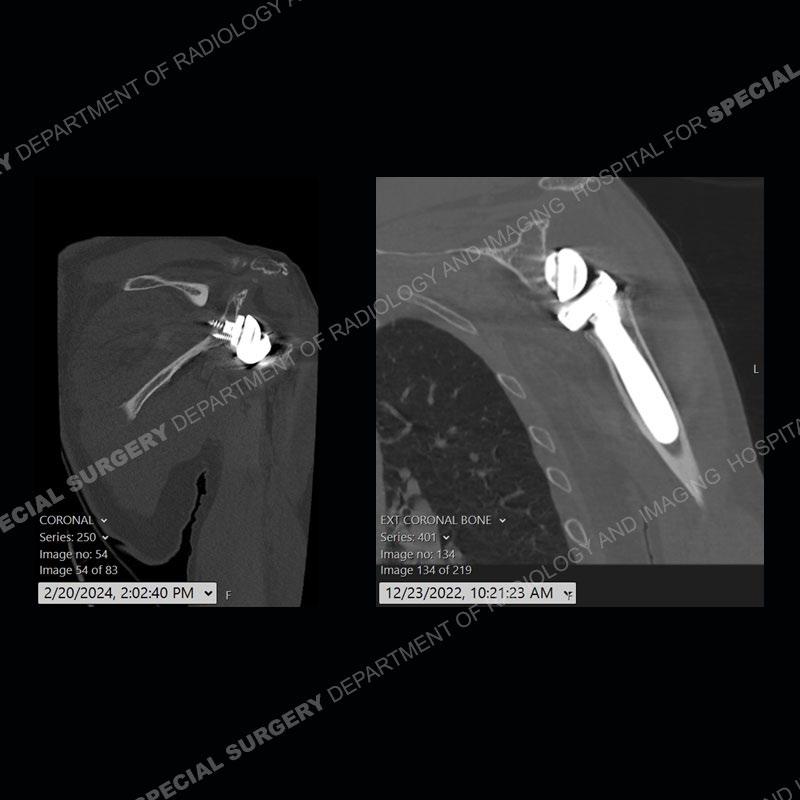

When comparing the radiographs, there is a slight change in the alignment in the components of the prosthesis. On the current radiographs, a radiolucent, crescentic focus is present at the level of the glenoid. When comparing the CT exams, there is a change at the alignment of the glenosphere and the humeral component and now a direct apposition of the components. On the current CT, the radiolucent, crescentic focus is again identified.

If comparison radiographs are present, subtle changes can be made more apparent. Instead of a space between the glenosphere and the humeral tray, there is a direct contact, and there may be an overall change in the alignment at the articulation. The displaced, radiolucent polyethylene liner depending on location can be seen on the radiographs, as in this case. At times, the liner may overlie other structures making identification very difficult on radiographs, but it should almost always be able to be identified on CT (as shown in this example as well). This patient is scheduled for revision procedure.